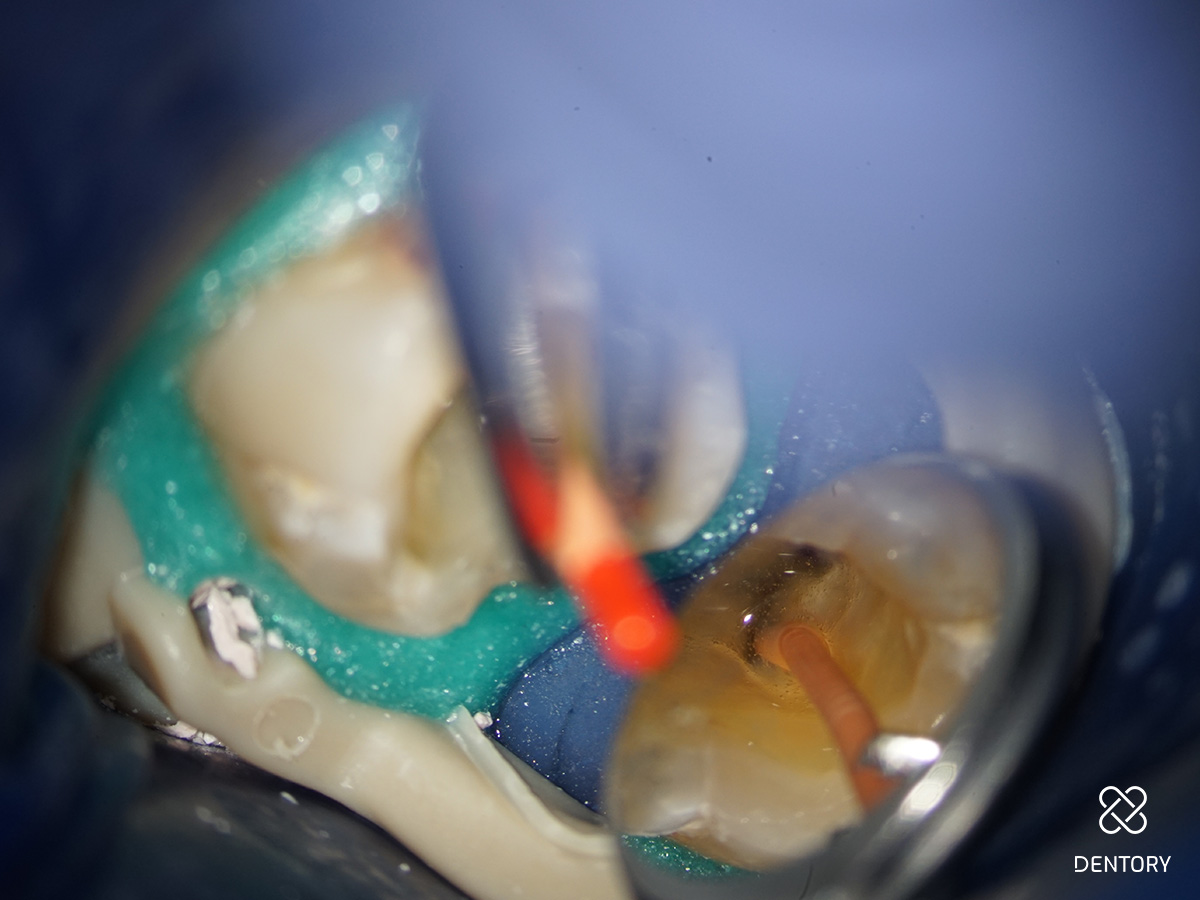

Abbildung 9

Agitation der Spülflüssigkeit: Diese eingepassten Mastercones eignen sich hervorragend, um die Spüllösung zu aktivieren.

Abbildung 10

MDA = „Manual dynamic agitation“: Durch ständiges schnelles Auf- und Ab- Bewegen des eingepassten Mastercones (Pumpen) in einem mit NaOCl gefluteten Wurzelkanalsystem kommt es zu einem 100%igen Austausch der Spülflüssigkeit, sodass frisches NaOCl in den schwer zugänglichen apikalen Kanalstrukturen desinfizierend wirken kann. Achtung: Pumpende Bewegung von 2-5 mm.